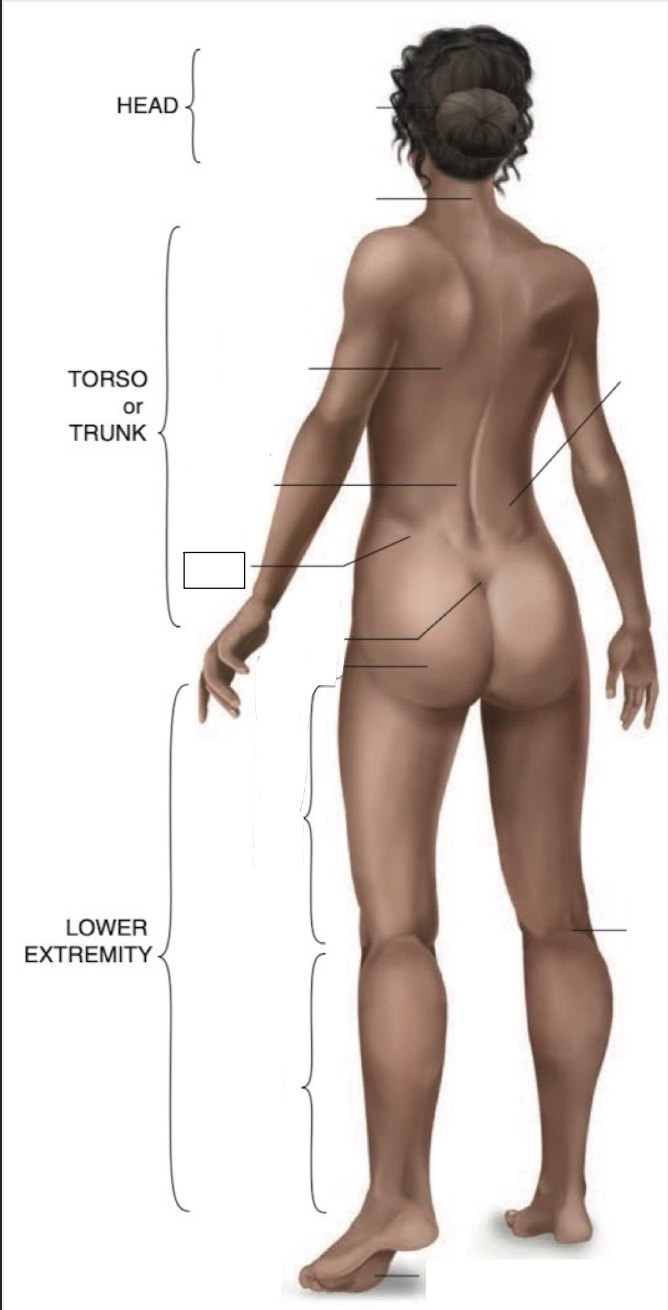

Occipital region

Cervical region

Inferior angle of scapula

Lumbar region

Iliac crest

Sacral region

Buttock

Flank